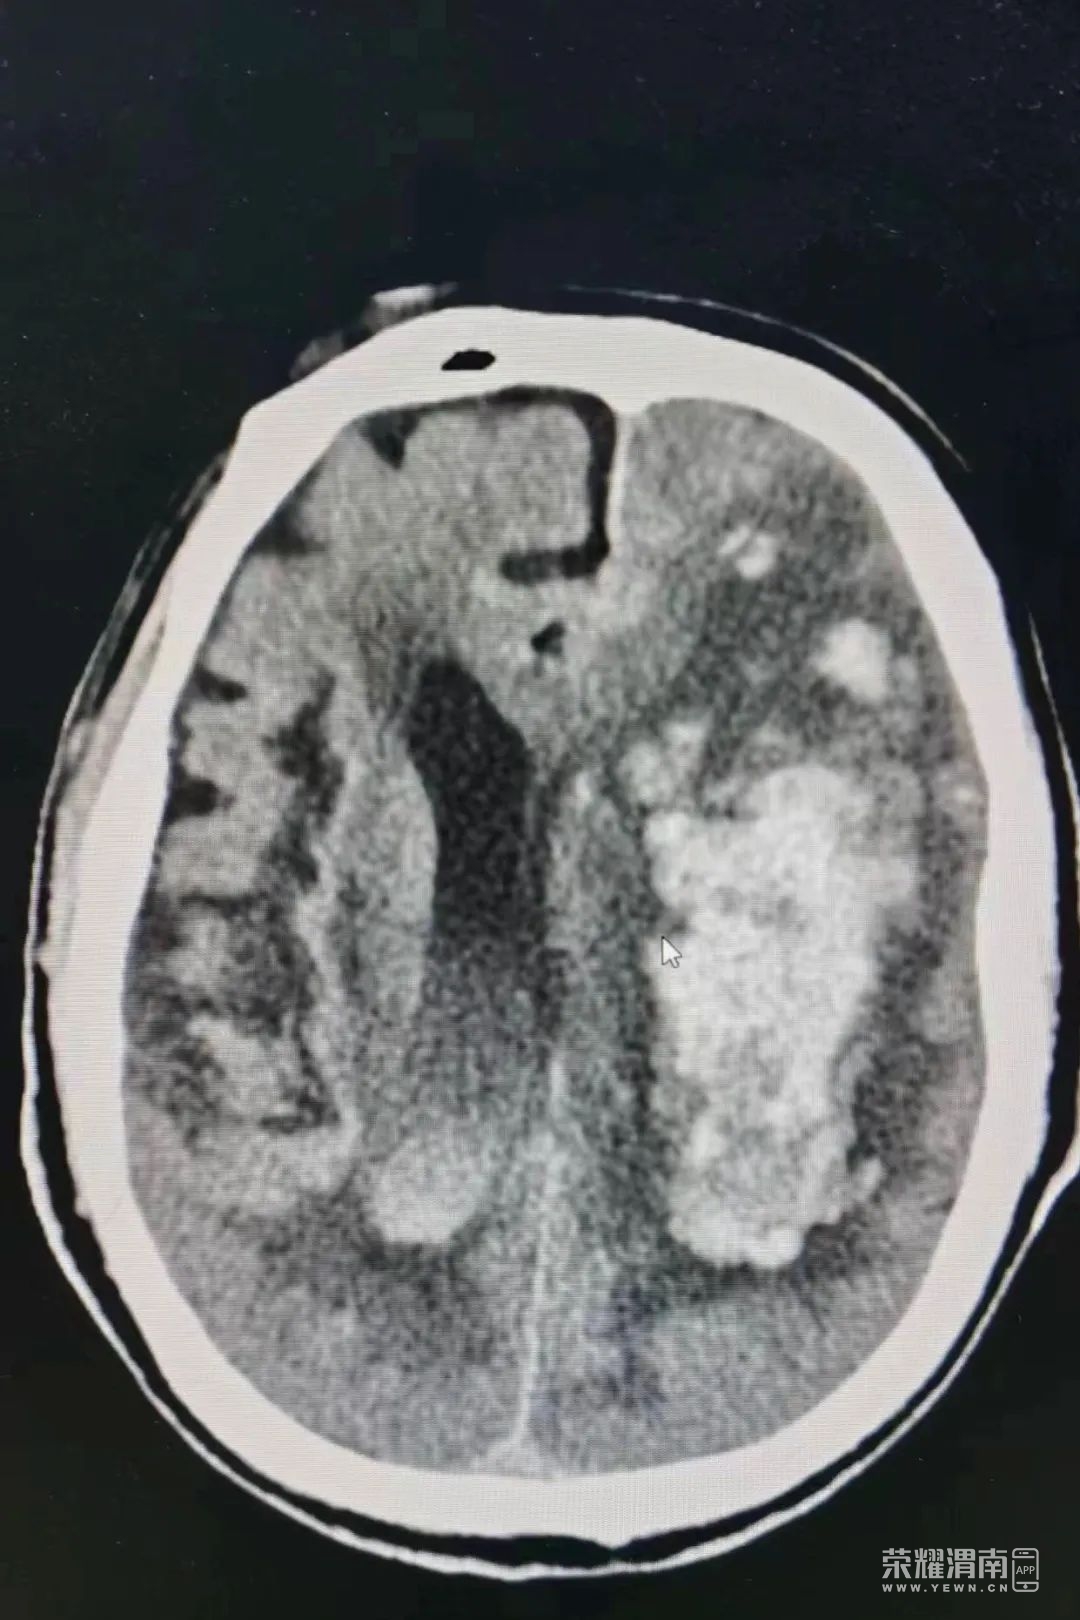

10:30患者入室,查阅病历:患者68岁,晨起跑步时无明显诱因突感恶心,呕吐,呕吐物为黄色胃内容物约100毫升

即出现言语不清,意识丧失,无胸闷气短,无腹胀腹痛。头颅CT显示:右侧基底节区脑出血(约50毫升)诊断为脑出血,患者两侧瞳孔已出现不等大,昏迷状态。情况十分危急。